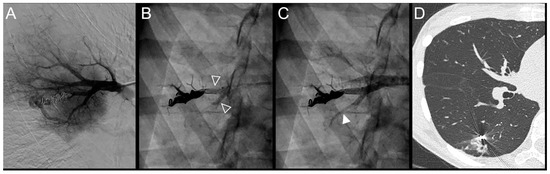

Figure 5.

Case example of a 37-year-old woman treated for a simple recurrent pulmonary arteriovenous malformation in the lower right lobe. Embolization was performed using Onyx® (0.5 mL) to fill the afferent artery within the pre-implanted coils and resulted in an immediate complete occlusion, maintained at 34 months follow-up. No leak in the aneurysm or in the vein was reported, but a leak in the upstream sub-segmental arteries was identified. (A). Opacification of the afferent artery showed a recanalization through existing coiling. (B). Opacity within and upstream of the pre-implanted coils (empty arrowheads) showed the distribution of Onyx®, with a leak in a proximal arterial branch. (C). Opacification of the afferent artery showed the absence of opacification of the aneurysmal sac and the efferent vein in favor of immediate occlusion. An altered opacification in the upstream branch (full arrowhead) was identified due to the leak of Onyx®. (D). The one-year follow-up chest CT showed a distal lung infarction related to embolization. Of note, the patient did not suffer from chest pain or pleural effusion after the embolization procedure.